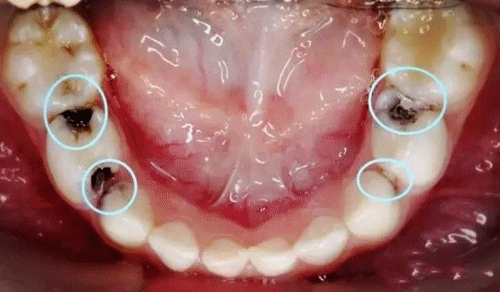

后槽牙蛀牙

求救前辈们!后槽牙蛀空,填补物脱落,18号才能看上,现在疼到升天.